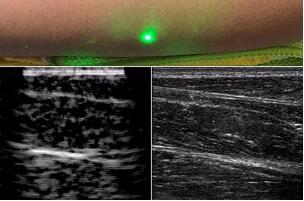

臨床應(yīng)用的無創(chuàng)超聲,要求探頭與人體皮膚直接接觸來向身體傳導(dǎo)高頻振動的超聲波。但是,有一些特定的患者卻在超聲檢查時受到限制,比如兒童、燒傷患者和敏感皮膚患者等。而近日麻省理工學(xué)院的研究人員證明,確實有可能使用激光在不接觸皮膚的前提下對患者進行超聲波掃描。

而麻省理工學(xué)院的研究小組現(xiàn)在開發(fā)了一種使用激光檢測皮膚上超聲波振動的方法,以便可以使用一種激光使皮膚產(chǎn)生共振,而另一種則可以檢測到振動,從而達到“遠程超聲掃描”的作用。

目前,研究人員已經(jīng)與健康的志愿者測試了他們的系統(tǒng):從半米遠處掃描了他們的前臂,并將這些結(jié)果與傳統(tǒng)超聲的結(jié)果進行了比較。他們能夠觀察到深達6厘米的組織,并能看到肌肉,脂肪和骨頭,并報告其結(jié)果可與標(biāo)準(zhǔn)超聲相媲美。

研究人員用一種激光裝置測試了這個想法,該裝置使用一個波長為1,550納米的脈沖激光來產(chǎn)生聲波,并使用第二個連續(xù)激光,調(diào)諧到相同的波長以遠程檢測反射的聲波。第二個激光器是靈敏的運動檢測器,可測量聲波從肌肉,脂肪和其他組織反射回來而引起的皮膚表面振動。反射的聲波產(chǎn)生的皮膚表面運動會導(dǎo)致激光頻率發(fā)生變化,這種變化可以測量。通過機械掃描人體上的激光,科學(xué)家可以獲取不同位置的數(shù)據(jù)并生成該區(qū)域的圖像。